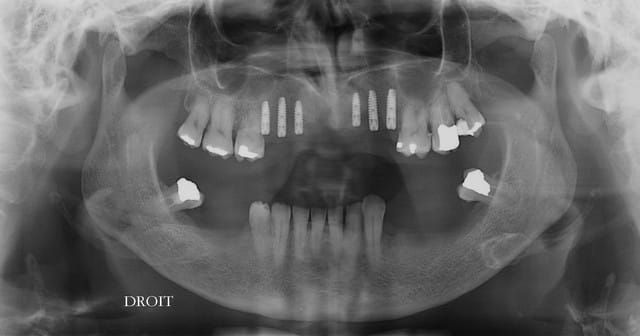

à 8 jours et pano et rétro pour compenser la déformation du pano

--

Je suppose que la patiente a un affreux stellite en bas ???

Dépêche toi de lui poser des implants car les stellites se tassent tjs et son bloc antérieur mandibulaire peut tout déchiquetter ton beau travail d implanto, d autant plus fort que tu n as pas épaissi secondairement ton mur vestibulaire que tu disais toi même manquer de bombé...